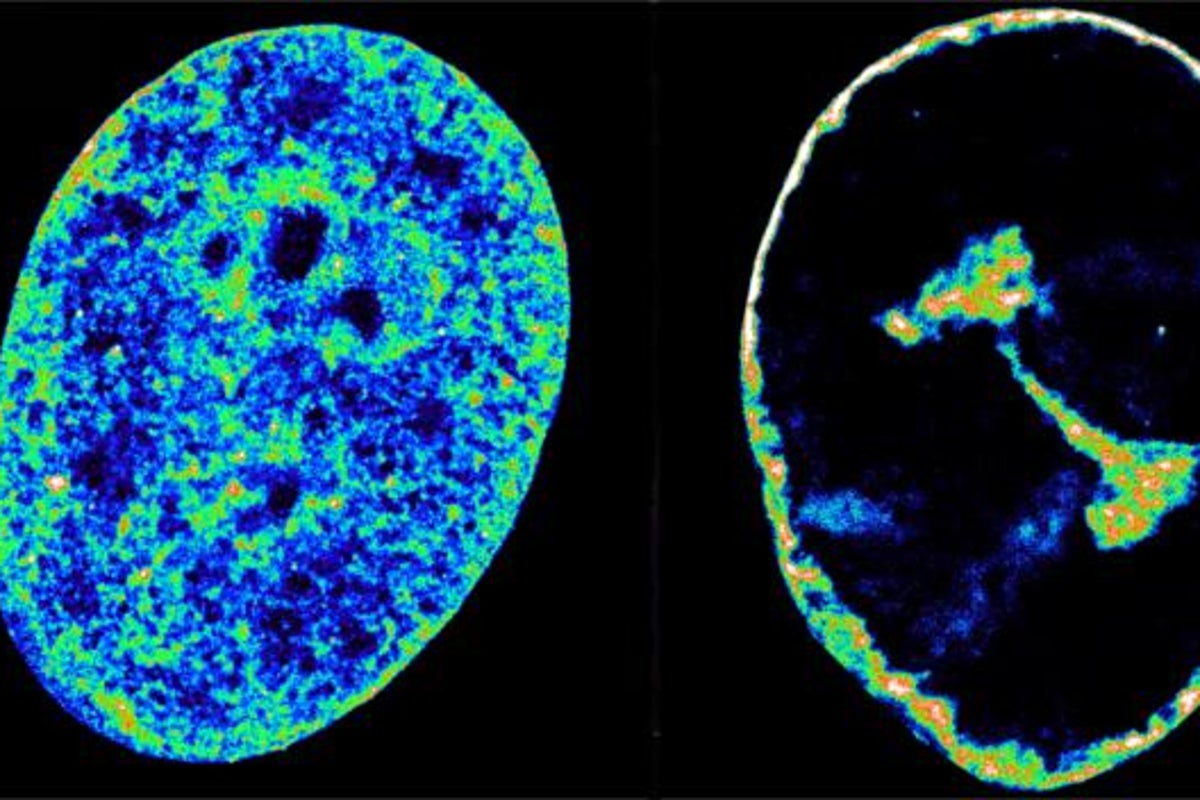

In the study, scientists used super-resolution microscopy to peer into ultra small cell structures just 20 nanometres wide, which is around 3,500 times thinner than a strand of hair.

They combined this with another technique that reveals which bits of DNA are touching inside the nucleus.

These techniques showed that the herpes virus’ hostile takeover begins within the first hour, with the virus hijacking a key human enzyme – RNA-polymerase II – to synthesise its own proteins.

Just three hours after infection, the virus causes a sizeable fraction of molecules involved in human DNA replication to abandon the cell nucleus and enter viral replication compartments.

The wholesale theft causes a collapse of any activity across the host genome, which then gets crushed into a dense shell just 30 per cent of its original volume.